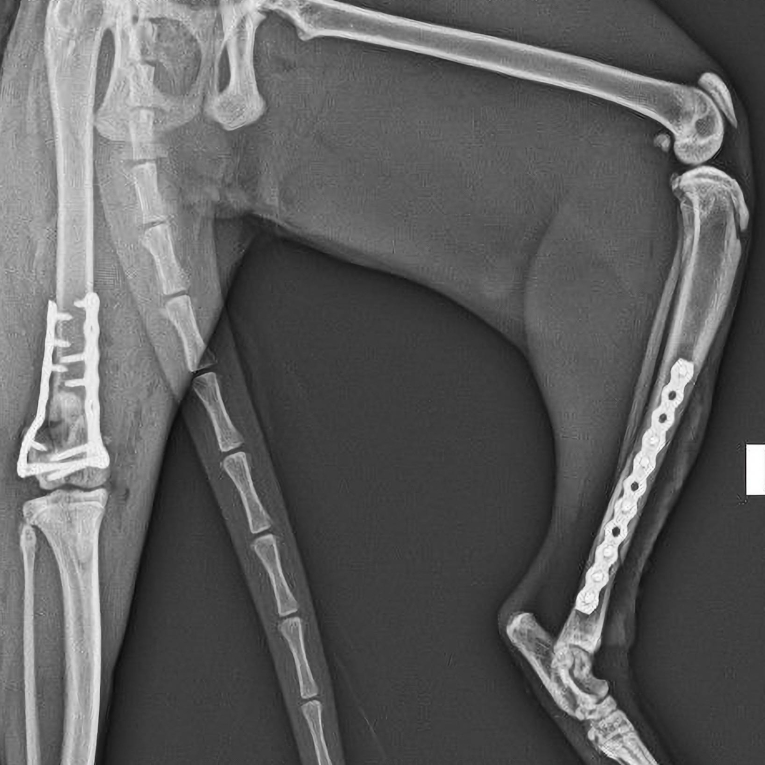

Tokyo, a 10-month-old mixed-breed cat, was presented to Veterinarium following severe trauma sustained from a fall from height.

Clinical and radiographic evaluation revealed:

- A comminuted distal physeal fracture of the right femur - Salter-Harris IV fracture (intra-articular involvement)

- A left tibial fracture classified as AO/OTA 42-A1 fracture

- The right femur was stabilized using dual locking plates and an additional interfragmentary compression screw

- The left tibia was stabilized using a locking titanium plate

The post is accompanied by a postoperative radiograph.